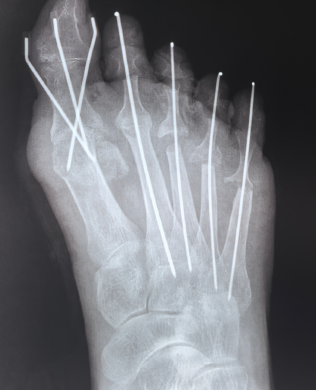

在应对复杂足部健康需求时,年轮医院医疗团队通常会采用多学科协作的模式,充分考虑个体的整体健康状况。例如以王阿姨例,30 年前即出现双足拇指外翻畸形,行走及运动后疼痛显著,经门诊检查确诊为 “双足跖趾关节病”,且患有类风湿性疾病。面对患者年龄大、病程长、合并症多的复杂情况,以闫超主任领衔的团队并未简单套用常规方案,而是通过多学科会诊反复研讨,zui终确定"单足多趾截骨矫形术",针对王阿姨单足 5 个脚趾共计 9 处截骨矫正手术,开展了精准的截骨矫形手术,以精细化操作攻克手术难题。此次手术的成功实施,不仅有效改善了王阿姨的足部畸形与疼痛症状,也体现了我院骨科在复杂足部矫形手术领域的专业技术实力。